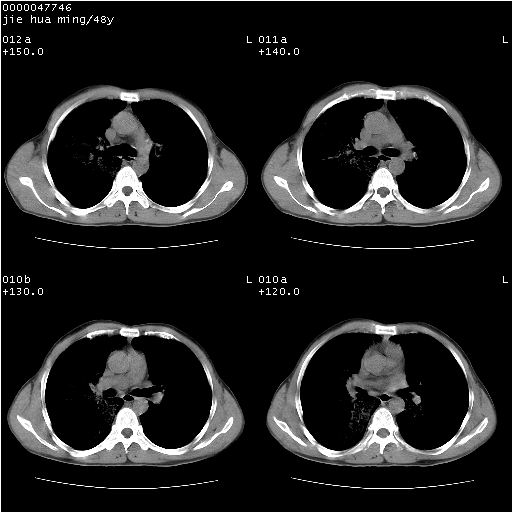

以下是引用dr.yang在2008-5-1 6:25:00的发言:[br]两肺广泛毛玻璃样的片状影,密度不均,边缘欠清,呈碎石路样改变,[br]考虑,1双肺间质性肺炎,2肺泡蛋白沉积症3支气管肺泡癌[br]

以下是引用hhcckk在2008-5-1 8:06:00的发言:[br]支持肺泡蛋白沉积症[br]依据:[br]1、病灶边缘清楚----地图征[br]2、病灶内部小叶间隔或小叶内间隔增厚所形成的网格状影----碎石路样表现[br]3、抗炎治疗无效(炎症抗炎治疗有效)[br]4、纵隔内未见肿大淋巴结(肺泡细胞癌时常有)[br][br]附肺泡蛋白沉积症资料[br][br]肺泡蛋白沉积症(pulmonary alveolar proteinosis)是一种原因不明的以肺泡腔内大量含脂糖蛋白样物质沉积为特征的疾病。[br]病理改变:(1)肺泡和细支气管腔内充满大量含脂糖蛋白样的粘稠物质,该物质为颗粒状或絮状的糖原pas染色阳性的磷脂蛋白。(2)肺泡壁及其间隔无异常改变。胸膜和淋巴结不受累及。(3)晚期可出现弥漫性肺间质纤维化。[br]临床表现:(1)好发年龄30~50岁,男性多于女性,偶见于儿童;(2)主要症状为呼吸困难、咳嗽、低热、消瘦、低氧血症和杵状指等。1/3的患者无症状。(3)实验室检查:痰液或肺泡灌洗液中可找到pas染色阳性颗粒物质。[br]hrct表现:肺泡蛋白沉积症具有特征性改变,即“碎石路样”表现(crazy-paving appearance,cpa)。主要包括(1)斑片状磨玻璃影:指肺野密度朦胧增加,内可见肺血管纹理影,系肺泡腔内充满低密度的磷脂蛋白物质所致。(2)其内部小叶间隔或小叶内间隔增厚所形成的网格状影,为小叶间隔水肿、肺泡壁内淋巴细胞和巨噬细胞浸润以及小叶内淋巴管扩张的缘故。(3)病灶边缘清楚,呈地图样分布于肺野外围或肺门及中央区。[br]

以下是引用zsl6918在2008-5-1 7:35:00的发言:[br]双肺磨玻璃样病变,可见铺碎路石征,病变区与正常区交错。边界清晰。符合肺泡蛋白质沉着征,高分辨扫描会更清楚漂亮。建议临床肺泡灌洗。

以下是引用yangyudong333在2008-5-1 5:36:00的发言:[br][br] 两肺广泛毛玻璃样的片状影,密度不均,边缘欠清,呈碎石路样改变,[br]考虑,1双肺间质性肺炎,2肺泡蛋白沉积症[br]